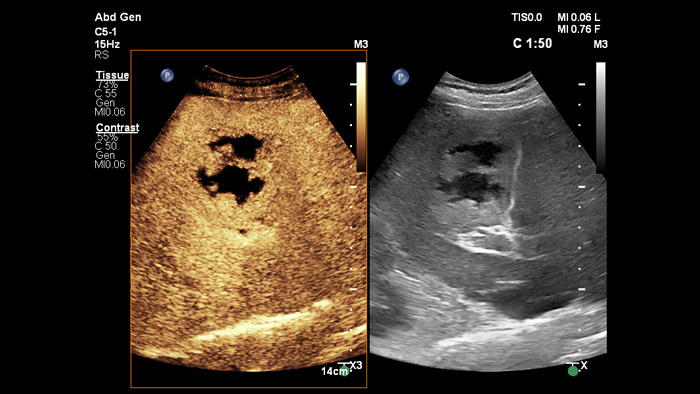

Los medios de contraste ecográficos pueden transformar el papel de la ecografía, de forma que los médicos puedan estudiar los patrones de realce de las lesiones hepáticas en tiempo real. Mediante los equipos ecográficos de Philips, los ultrasonidos con contraste mejorado se integran a la perfección en el flujo de trabajo estándar.